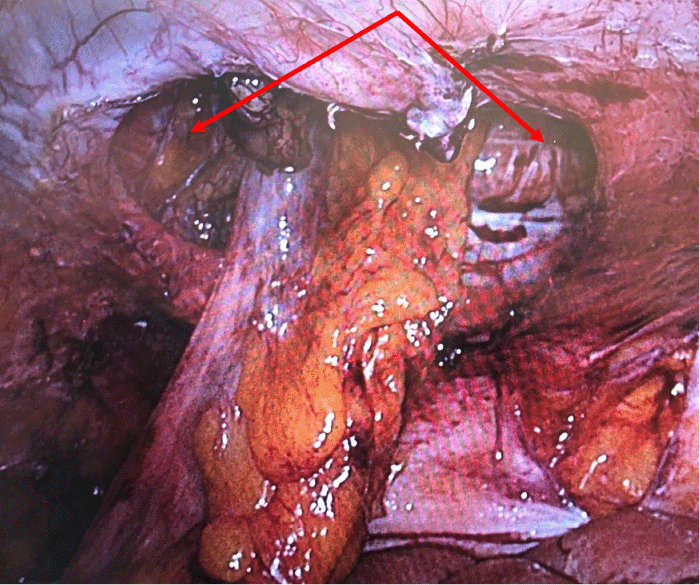

On presentation, vital signs were stable, and physical examination revealed a large, non-reducible, non-tender parastomal bulge. Laboratory findings were notable for leukocytosis (17.6 × 109/L), hypochloremia (95 mmol/L), hypokalemia (3.0 mmol/L), and mild lactic acidosis (2.5 mmol/L). CT scan of the abdomen demonstrated a left lower quadrant parastomal hernia containing small bowel loops, the gastric body, and the pyloric antrum. Gastric distention with air-fluid levels and a decompressed duodenum indicated a high-grade gastric outlet obstruction, with the transition point in the herniated stomach (Figure 1).

Figure 1. CT Scan of Stomach Herniation (arrows) Within Large Parastomal Hernia in LLQ (arrows). Published with Permission

(A) Axial and (B) sagittal views